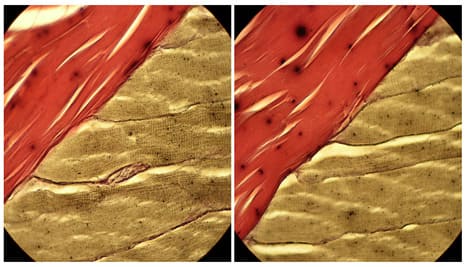

Own longitudinal and transverse specimens of the rat triceps surae muscle Gomori and Azan stained and US images of normal muscles. They were analyzed to visualize and confirm or deny knowledge about striated muscles’ tendinous system. Tendinous system consists of tendons, endomysium and perimysium (Figures 1,2). Within any striated muscle understood as a structure between origin and insertion there is no place where there wouldn’t be a tendinous tissue. So muscle in fact is a tendon delaminated at the belly level to host myofibers (Figure 2).

Histological specimens show that the tendons loose their mass as they go along the muscle belly (Figure 3). That is due to the fact that tendinous fibers detach from the tendon and without any junction cover the whole myofiber as loose connective tissue (Figures 4,5).